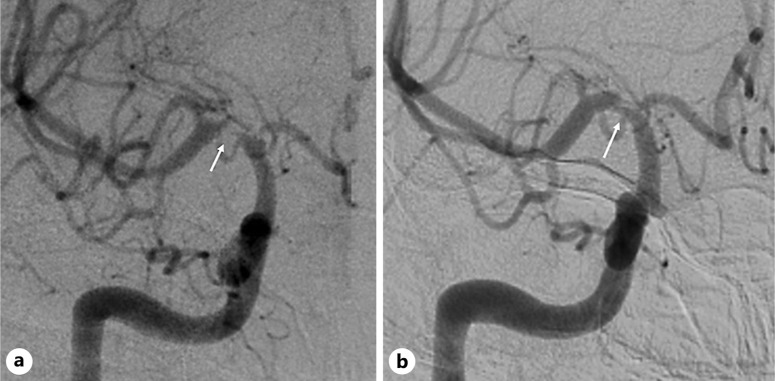

Results: We identified 10 patients (9 males) with FCA giving an incidence rate of 2.8 per 1,000 person-years. Nine patients had an ischemic presentation (transient ischemic attacks = 5, minor strokes = 3, and major stroke = 1), while 1 patient had a cortical subarachnoid hemorrhage. The supraclinoid ICA and proximal middle cerebral artery (MCA) were the most common segments involved. Nine patients were treated with antiplatelets, and 3 received additional steroids. All cases underwent MRVWI, with concentric wall enhancement noted in most (80%). Follow-up imaging showed improvement in stenosis in 2 patients and a reduction in vessel wall enhancement in 3 patients. Except for the patient with a major stroke, all others had excellent short- and long-term outcomes with no recurrence of ischemic events. The presence of vessel wall enhancement did not predict short- or long-term outcomes.

Conclusion: FCA is a rare cause of young stroke that preferentially involves the supraclinoid ICA and proximal MCA with excellent outcomes. MRVWI can be useful in ruling out mimics, but the presence of contrast enhancement did not predict outcome.